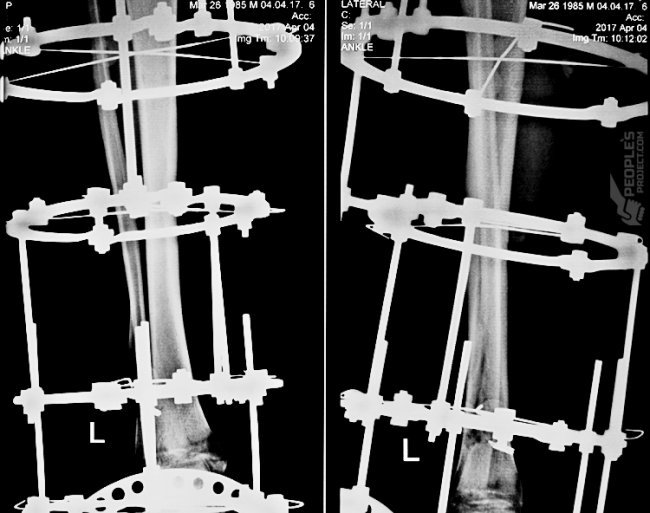

Обстеження показало: артродез гомілково-ступневого суглобу фактично відбувся, тож лікарі негайно демонтували частину масивного апарату зовнішньої фіксації, у який повністю закуто усю ліву ногу чоловіка. Основний етап лікування у Сергія ще попереду, коли нога трошки зміцниться, лікарі компенсують значний кістковий дефект за допомогою клітинних технологій. Практика показує: таке інноваційне лікування повертає майже безнадійних поранених до нормального життя.

У рамках «Біотеху» Сергієві трохи витягнуть ногу, зростять потрощені кістки за допомогою клітинних техологій. Вибух пошкодив один із важливих нервів, тож стопу довелося зафіксувати методом артродезу. Вже трохи згодом, коли нога відновиться, лікарі візьмуться і за потрощену руку – травма п’ястної кістки дозволяє поки що зачекати.